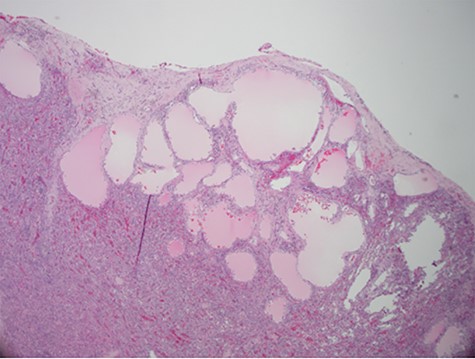

Despite aggressive resuscitation, the patient’s hemodynamics and clinical exam declined. He was taken emergently to the operating room for exploratory laparotomy, evacuation of hemoperitoneum and splenectomy. The spleen was noted to have an isolated nodular, cystic appearing portion in addition to large area of capsular tear. In total, he received four units of PRBC, four units of fresh frozen plasma and one unit of platelets peri-operatively; however, he continued to show signs of hemorrhagic shock. Morning lab-work revealed a Hgb of 5.9 mg/dL from 7.6 mg/dL despite two additional units of PRBC on post-operative day one. Due to continued decline in Hgb and ongoing tachycardia, he returned to the operating room on post-operative days two and four for repeat exploration. Each procedure failed to identify an obvious source of bleeding, except for diffuse oozing in the peritoneal cavity. Further family discussion revealed a history of Hemophilia A in the patient’s brother, diagnosed during childhood. New diagnostic workup was obtained and was consistent with a variant of Hemophilia A. He was subsequently treated with recombinant Factor VIII to a goal of 80–100%, per hematology recommendations, and underwent definitive closure with hemostasis noted on post-operative day six. Pathology report returned as a ruptured spleen with hemorrhage and a subcapsular nodule with dilated lymphovasculature consistent with splenic lymphangioma (Figs 2 and 3).

Hematoxylin and eosin stain photomicrographs from splenectomy consistent with splenic lymphangioma with 10x magnification.

Isolated splenic lymphangiomas are most often an incidental radiologic finding, as most are asymptomatic [2, 3]. CT typically shows single or multiple low density, thin walled, sharply marginated subcapsular cyst(s) [2]. There is no contrast enhancement and the presence of curvilinear, peripheral mural calcifications is further supportive of a cystic lymphangioma [2]. Differential diagnosis may include hemangioma, epidermoid cyst, mesothelial cyst and parasitic or hydatid cysts; with histopathologic examination required for definitive diagnosis [1–4]. Histologic analysis often consists of a single layer of flattened endothelium lined spaces, filled with eosinophilic proteinaceous material instead of blood as in a hemangioma [2].